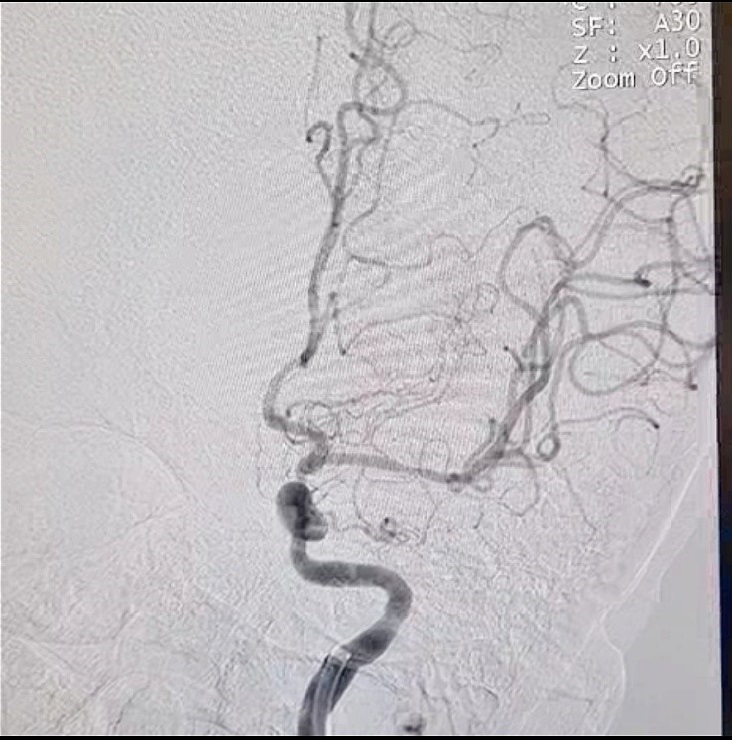

Chỉ trong vòng 30 phút kể từ khi nhập viện, bệnh nhân đã được làm các chỉ định cận lâm sàng cần thiết. Kết quả chụp MRI 1.5 Tesla mạch não và dựng hình mạch máu não của bệnh nhân cho thấy hình ảnh hẹp tắc toàn bộ động mạch cảnh trong bên trái kèm theo xơ vữa động mạch. Các bác sỹ chẩn đoán bệnh nhân bị nhồi máu não cấp do huyết khối động mạch não, nếu không được can thiệp khẩn cấp cơ hội tái thông là rất thấp và nguy cơ có thể tử vong.

Ngay sau đó, bệnh nhân được chuyển thẳng vào phòng can thiệp, các bác sỹ thuộc ê kip can thiệp đã tiến hành luồn catherte vào động mạch đùi, tiếp cận được cục máu đông, sử dụng dụng cụ cơ học Solitaire để lấy cục huyết khối.

Sau hơn 2 giờ can thiệp, kết quả đánh giá lại cho thấy bệnh nhân tỉnh, tiếp xúc tốt, nói rõ chữ, không còn liệt vận động nửa người phải. Sau 5 ngày điều trị, bệnh nhân hồi phục sức khoẻ tốt, tự sinh hoạt đi lại bình thường và đã được ra viện.

Hình ảnh tắc mạch máu não

Hình ảnh sau can thiệp được tái thông